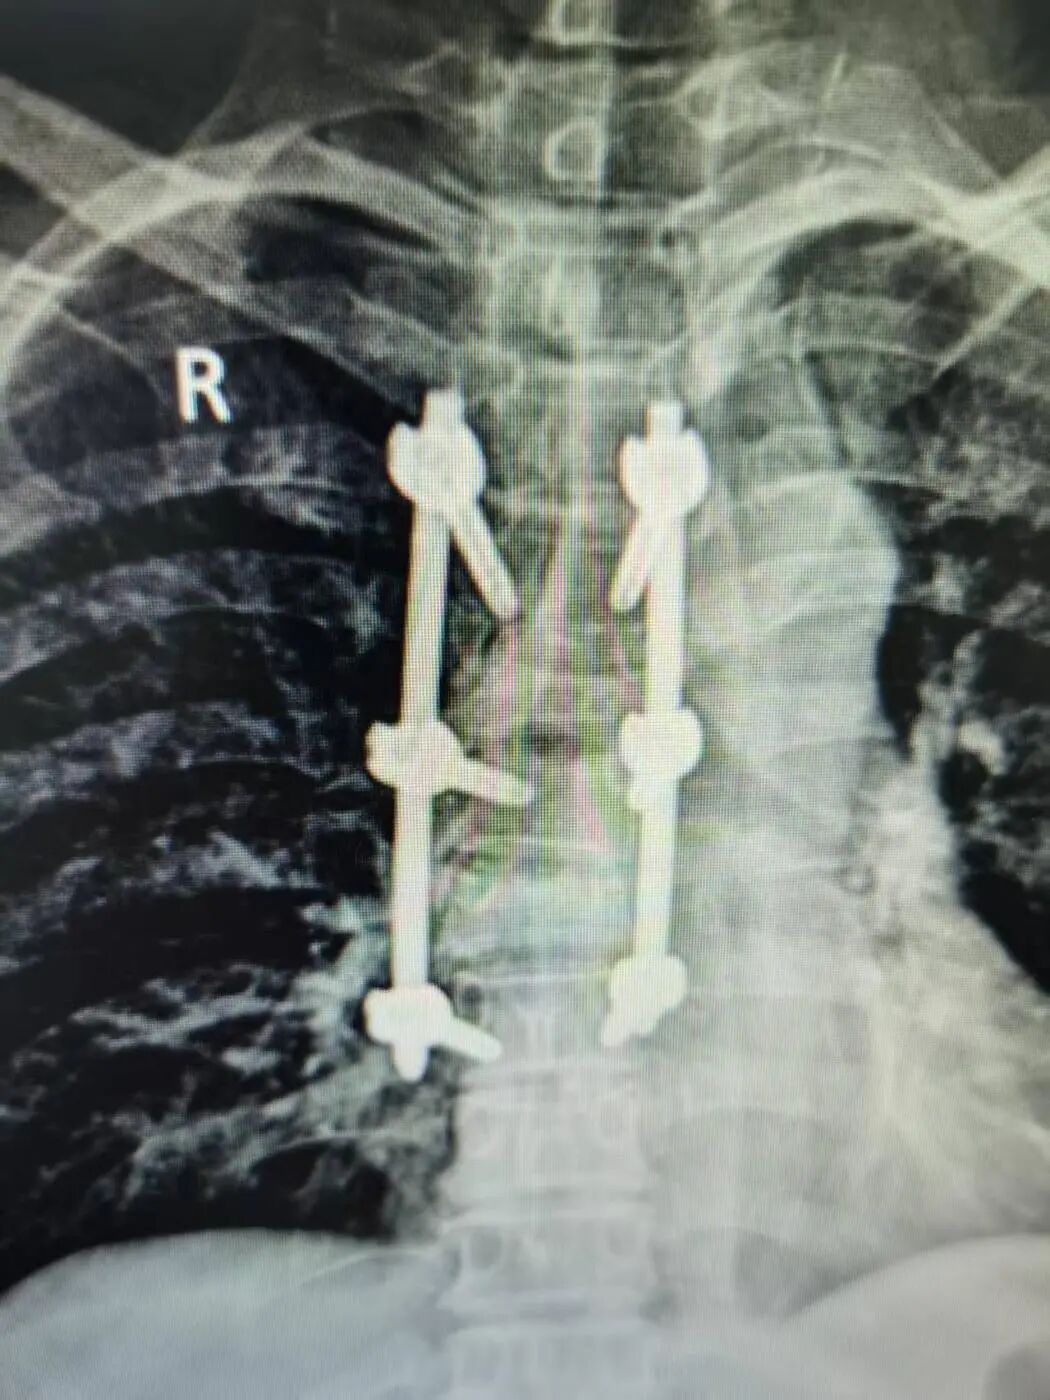

签约仪式后,朱卉敏教授团队立即开展手术演示。手术针对一名多发胸椎椎体骨折患者。一直以来,胸椎尤其是高位胸椎手术因解剖结构复杂、毗邻脊髓与大血管,稍有不慎,极易损伤神经导致瘫痪,容错率几乎为零,向来是脊柱外科的“禁区”与难点,令无数医师畏之如虎、知难而退。

朱卉敏教授团队一边操作,一边为现场观摩的福鼎市医院骨科团队详细讲解解剖标志、操作要点与风险规避技巧。手术过程流畅、视野清晰、出血极少,历时约50分钟,手术顺利完成。术后患者即刻苏醒,次日即可下床活动,疗效显著获得在场医护人员与患者家属的高度赞誉。